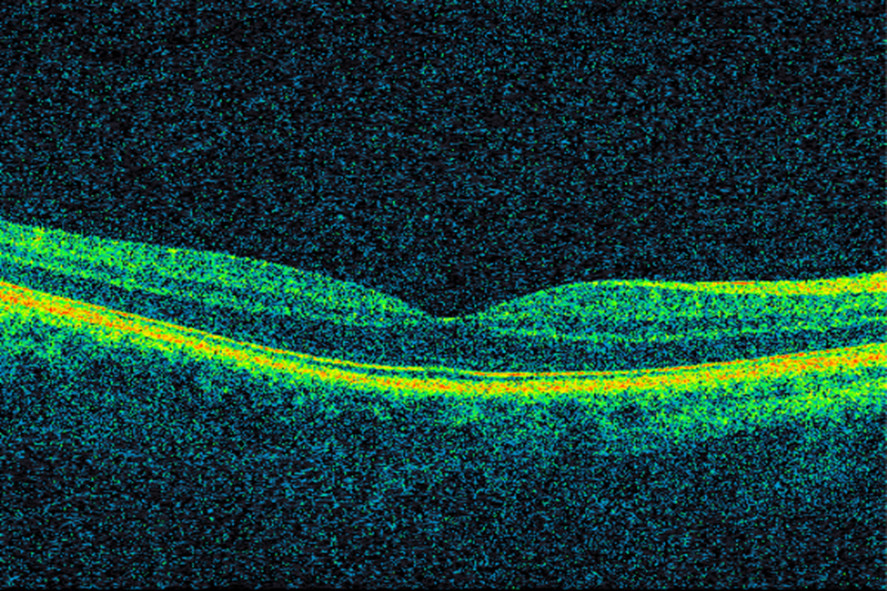

Huang D, Swanson EA, Lin CP et al. Optical coherence tomography. Science 1991; 254: 1178 - 81. [PubMed][CrossRef]

Rosenfeld PJ, Moshfeghi AA, Puliafito CA. Optical coherence tomography findings after an intravitreal injection of bevacizumab (avastin) for neovascular age-related macular degeneration. Ophthalmic Surg Lasers Imaging 2005; 36: 331 - 5. [PubMed]